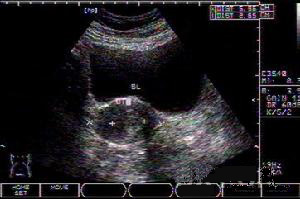

2、B型超聲檢查示子宮增大,宮腔內有液性暗區,內有強光點。

宮腔子宮頸癌在女性生殖系統惡性腫瘤中占首位。由於宮頸易於暴露,可以直接進行細胞學及活體組織檢查,因而超聲一般不作為其首選及必行檢查。而對於宮頸癌合併宮腔內積膿的患者,臨床上多需行超聲檢查以進一步鑑別診斷。

宮頸癌合併宮腔積膿一般沒有特異的臨床表現。超聲表現為子宮體增大,宮腔內充滿液性暗區,暗區內散在疏密程度不等的點狀回聲,積膿較重時肌層受壓變薄。宮頸可表現為正常回聲、不均質回聲或出現異常結節。

超聲對於宮腔積膿的診斷較容易,而要確定是否為宮頸癌所致則較難,在以下情況下應考慮宮頸癌合併宮腔積膿的診斷:(1)老年患者出現宮腔積膿;(2)宮腔積膿而宮體內膜均勻且不增厚;(3)宮腔積膿合併宮頸部回聲異常。

宮頸癌並宮腔積膿應注意與子宮內膜癌合併宮腔積膿鑑別。子宮內膜癌患者多有絕經後陰道出血和陰道排液;聲像圖除宮腔積膿外還表現為子宮內膜瀰漫性不均勻增厚(可達0.6cm以上),或呈團塊狀,子宮肌層常有浸潤,出現不規則異常回聲。患者術前可能被誤診為盆腔囊腫,這是因為子宮體完全失去正常回聲而呈薄壁樣囊性腫塊,此病例提醒我們當老年人發現盆腔內囊性腫塊時應考慮到宮腔積膿的可能性,此時應仔細觀察子宮的情況及與囊性腫塊的關係,以免誤診。